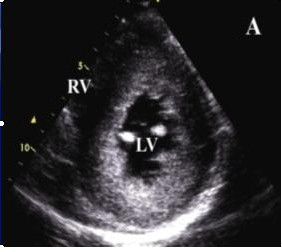

1.擴張型心肌病早期即可見心腔輕度擴大,尤其是左心室,室壁運動減弱,後期各心腔均擴大,室間隔及左室後壁運動也減弱,二尖瓣前葉雙峰可消失,而前後葉呈異向活動,左心室噴血指數常減至50%以下,心肌縮短比數也減小,可有少量心包積液。

2.肥厚型心肌病可見不對稱性室間隔肥厚,室間隔厚度與左室後壁厚度之比大於1.3:1;二尖瓣前葉收縮期前移;左心室腔縮小,流出道狹窄;左心室舒張功能障礙,包括順應性降低,快速充盈時間延長,等容時間延長等。